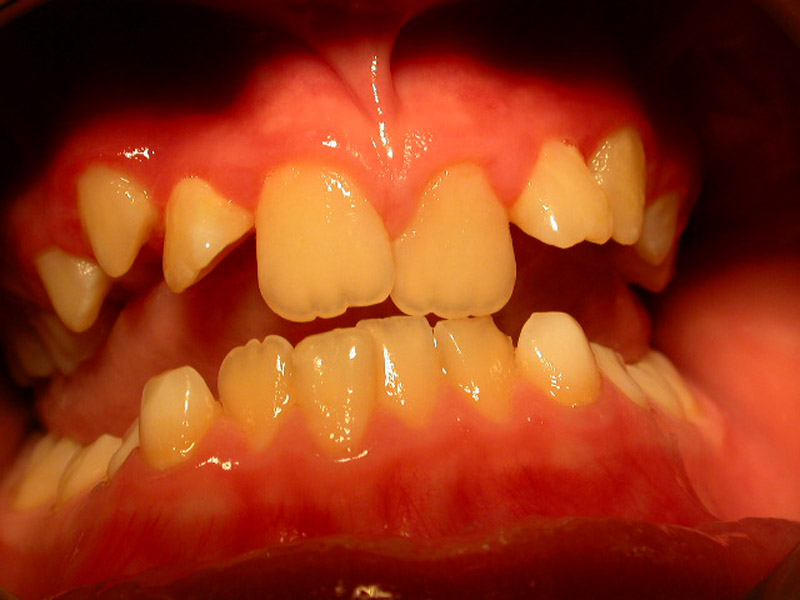

Αισθητικά προβλήματα – εκτός από τα ορθοδοντικά – προκύπτουν και από χρωστικές που επικάθονται στα δόντια. Η χρωστική αυτή πολύ συχνά είναι μαύρη (μελανή χρωστική) και οφείλεται στα λεγόμενα χρωμογόνα μικρόβια. Επίσης, όχι και πολύ σπάνια, υπάρχουν αισθητικά προβλήματα από μη τέλειο σχηματισμό της αδαμαντίνης, πριν ακόμη ανατείλουν τα δόντια (Υπενασβεστίωση τομέων-γομφίων, ατελής αδαμαντινογένεση κλπ).

Interceptive Orthodontics